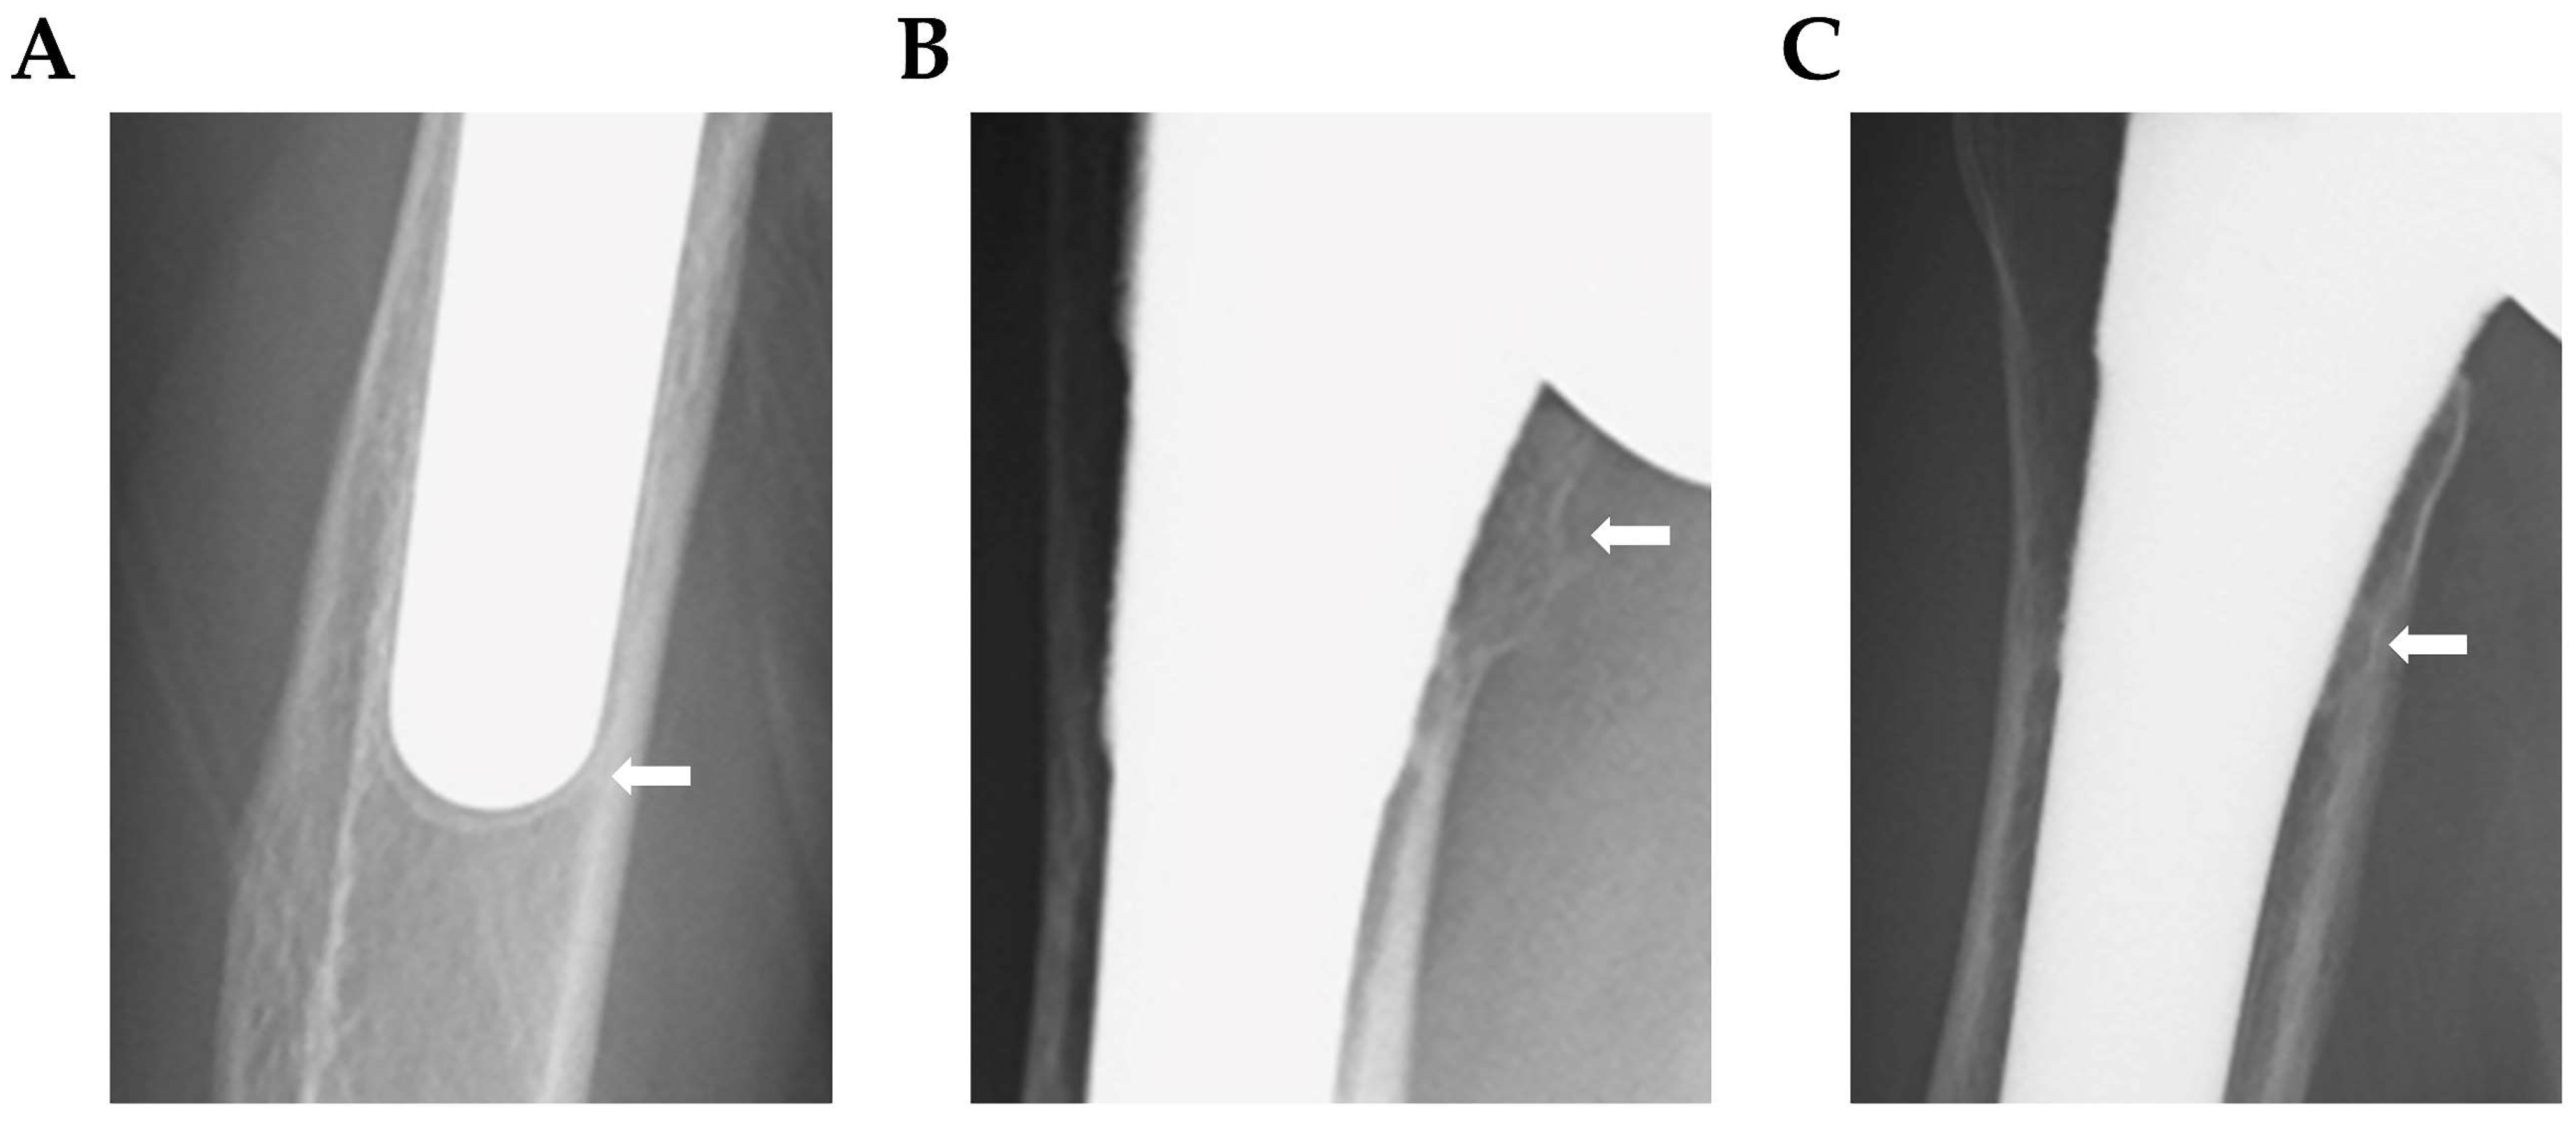

3.1. Evaluation at 1 Year after Surgery Using Plain Radiography

| Bone resorption | 5 (13.5%) | 6 (16.2%) | 0 | 0 | 16 (43.2%) | 19/37 (51.4%) |

| Lucent line | 0 | 0 | 5 (13.5%) | 0 | 0 | 5/37 (13.5%) |

| Spot welds | 0 | 6 (20.7%) | 0 | 14 (48.2%) | 0 | 14/29 (48.2%) |